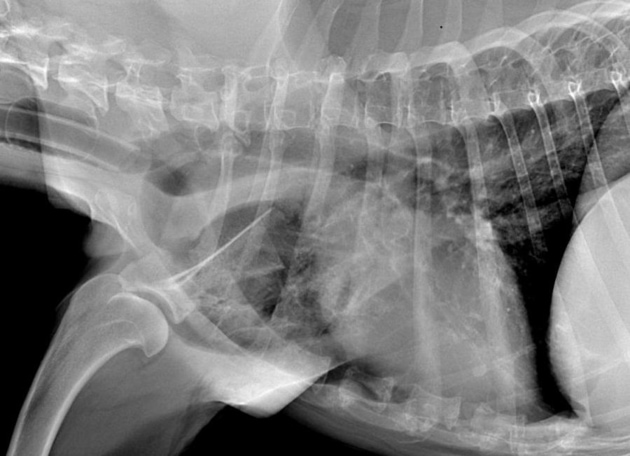

Cinq mois après l’intervention, la chienne est revue en consultation pour détérioration de l’état général et appétit sélectif depuis 10 jours. Une faiblesse généralisée est présente, une dyspnée, une discordance ainsi qu’une légère tachypnée sont notées. Les propriétaires rapportent que la chienne utilise sont membre normalement mis à part le mouvement de circumduction de l’épaule qui n’a jamais disparu. La palpation ne permet pas de mettre en évidence une éventuelle récidive locale de la tumeur ce qui est confirmé par la réalisation de radiographies vigiles (fig. 11).